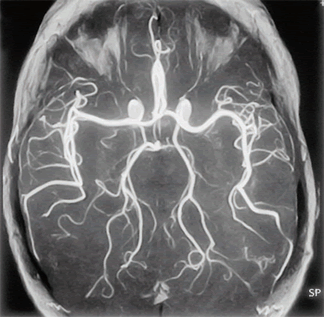

Ангіографія судин головного мозку - об'ємне зображення

Це надає можливість високоякісної візуалізації всіх структур і характеру кровотоку в межах судин головного мозку та шиї. Магнітно-резонансна томографія ангіографічної типу від звичайного МРТ дослідження відрізняється отриманням в кінці процедури тривимірного об'ємного зображення вен і артерій.

Судини головного мозку при МРТ

З його допомогою відкривається можливість діагностування кровопостачання в динаміці, виявлення ледь помітних патологічних процесів на самих ранніх етапах формування. Окремим плюсом МРТ ангіографії судин головного мозку є можливість стеження за особливостями кровотоку пацієнтів, у яких попередньо стався інсульт.